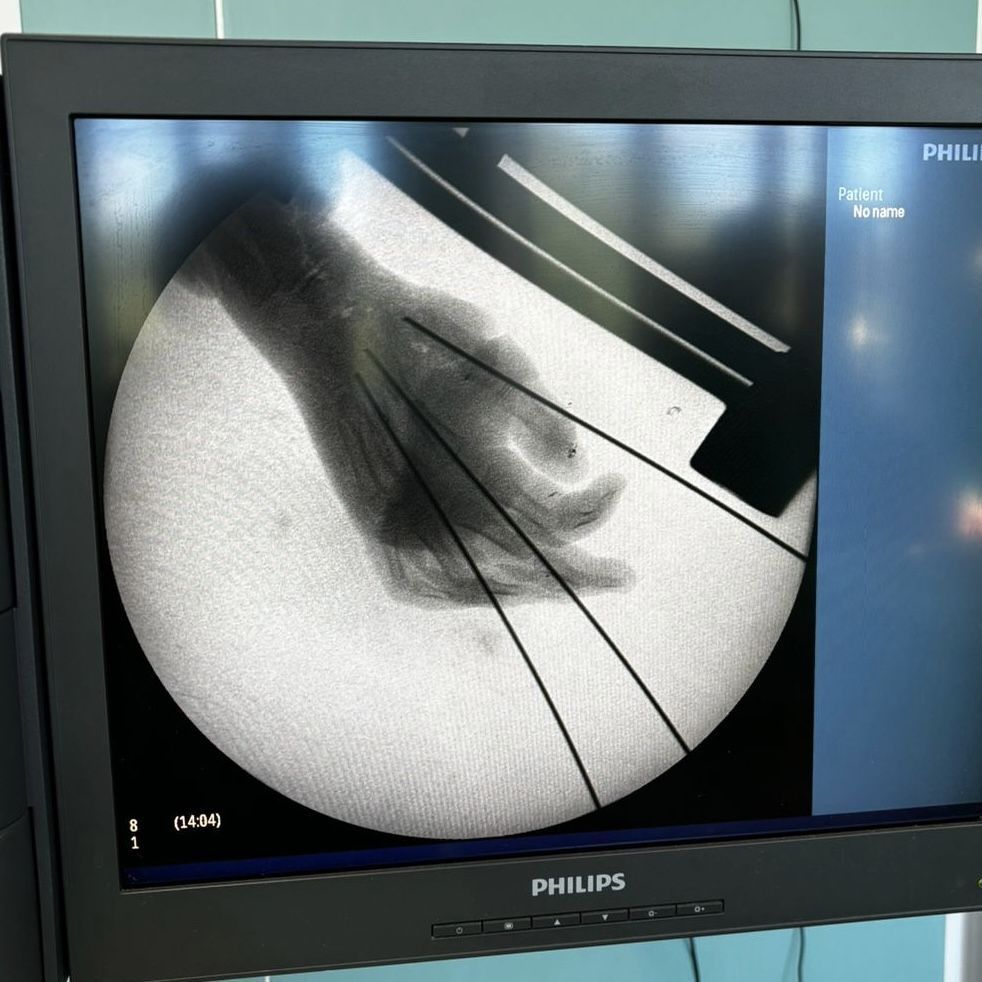

Врачебная команда провела репозицию осколков первой, второй и третьей пястных костей, фиксируя их спицей Киршнера диаметром 2,0 мм, с учетом необходимой компрессии.